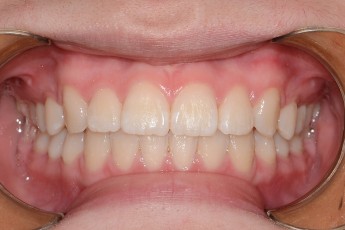

Before

After